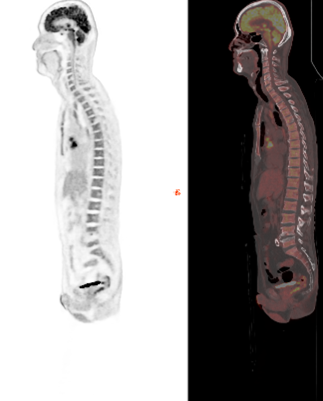

Precision DL (PET/CT) enhances image quality in PET/CT scans, providing clinicians with a powerful solution to aid in precise diagnoses, treatment planning and monitoring with the image quality performance benefits typically associated with hardware-based Time-of-Flight (ToF) reconstruction, without compromising sensitivity, including improved contrast-to-noise ratio, contrast recovery,[xii] and quantitative accuracy.[xiii]